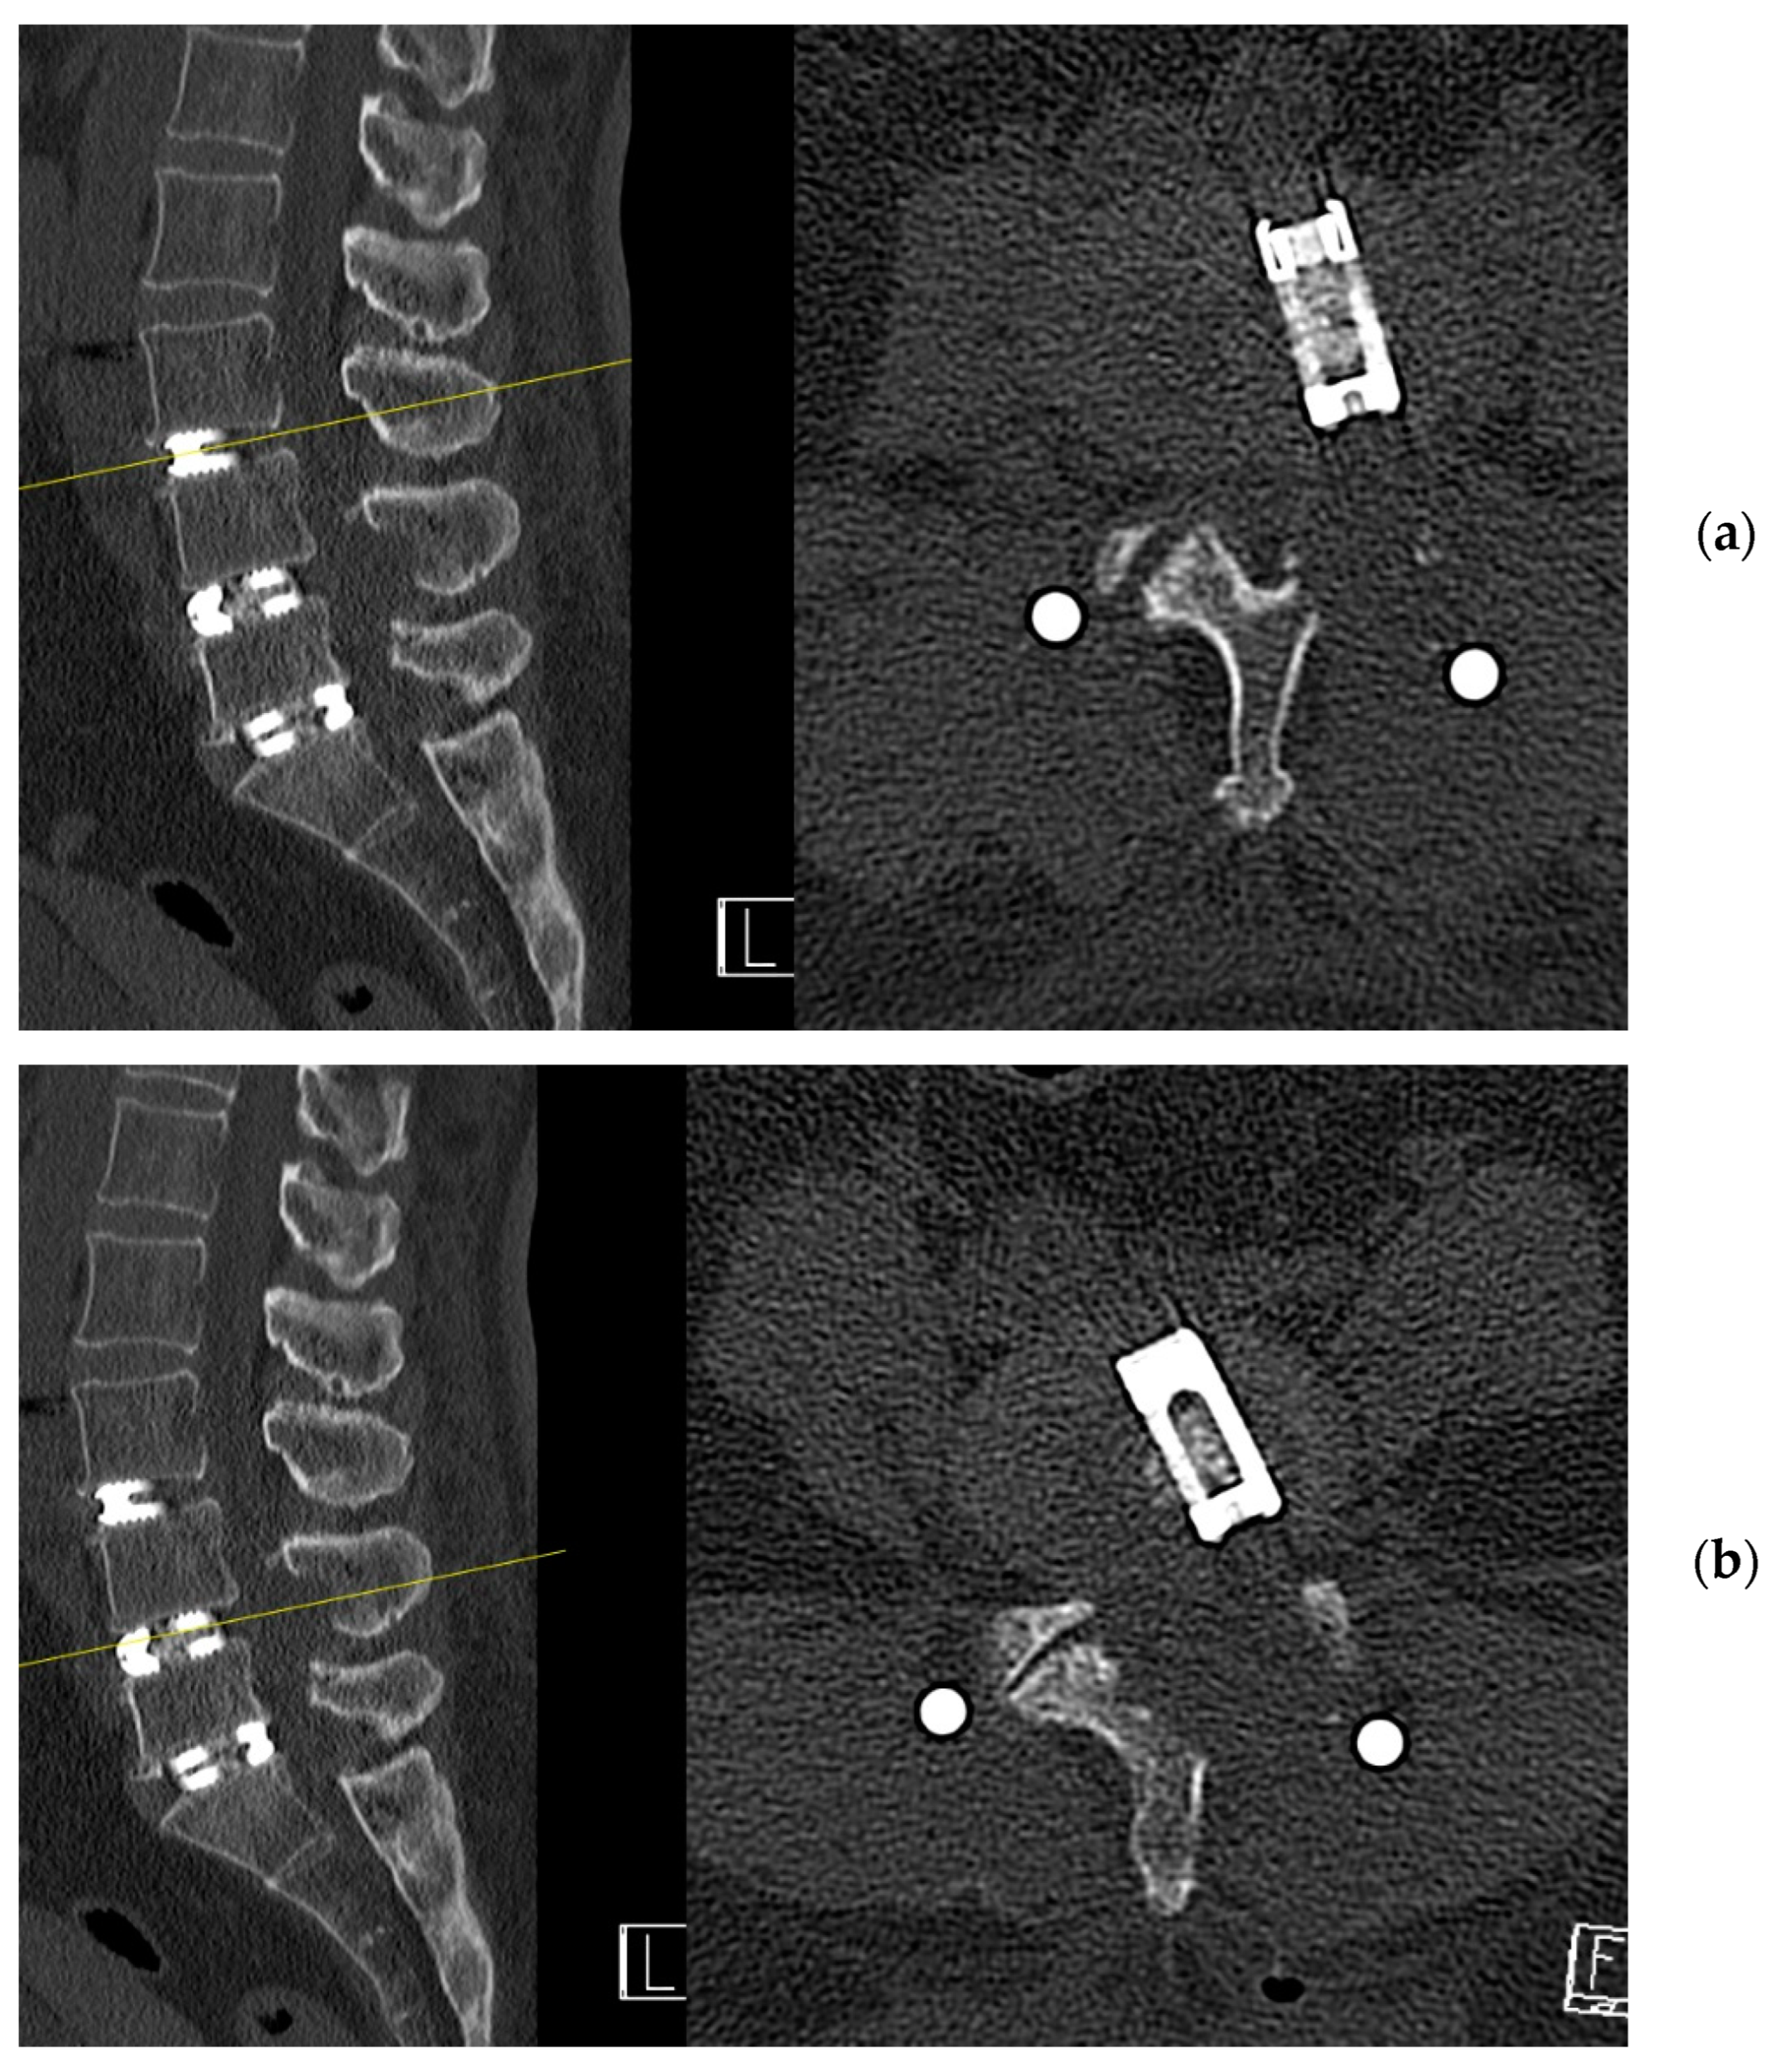

4.1. Case 1: Madam M

4.2. Case 2: Madam R

4.3. Case 3: Madam M